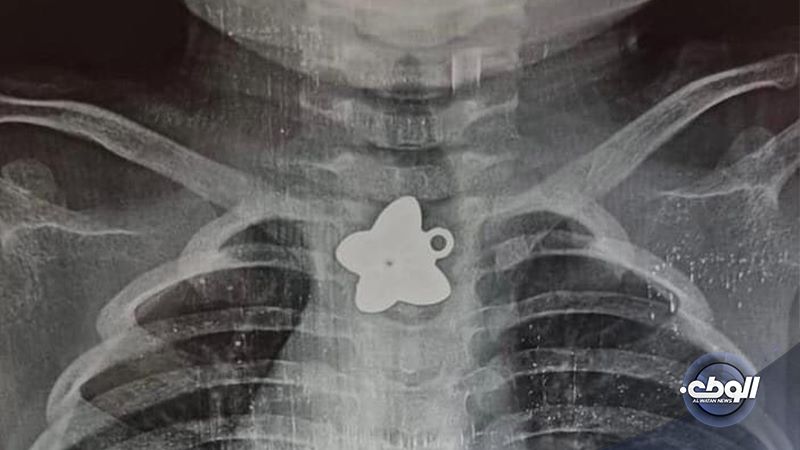

استقبل قسم الأنف والإذن والحنجرة بمركز البيضاء الطبي، صباح اليوم الجمعة، حالة محولة من مدينة درنة، لطفل يبلغ من العمر سنة ونصف، يشتكي من وجود جسم غريب في المريء.

وحسب بيان المركز، فقد تبين بعد الكشف وجود جسم غريب داخل مريء الطفل، حيث قام الطاقم الطبي بإجراء عملية لاستخراج الجسم الغريب، وذلك بمنظار المريء تحت التخدير العام.